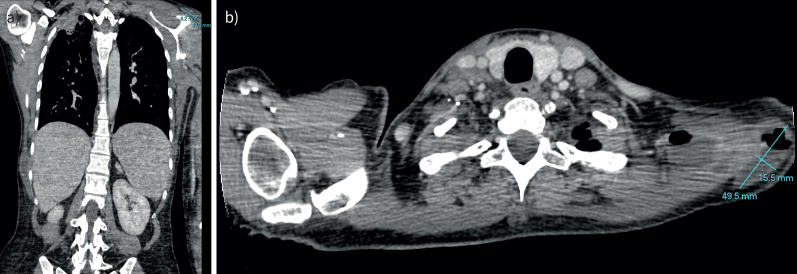

A 40-year-old woman begins to have breathing difficulties after a history of ophthalmological issues. She then has a complex and complicated clinical course with multiple interesting diagnoses and treatments, with much to be learnt along the way. https://bit.ly/4gIolF8.